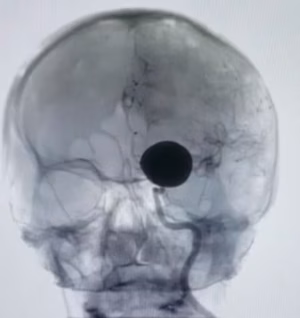

Como evitar e tratar a plagiocefalia posicional em bebês.

Sobre a Malformação de Chiari e seu tratamento.